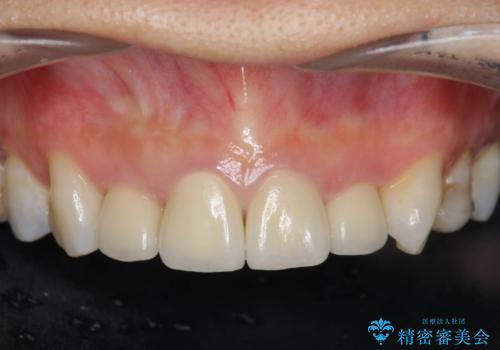

自然で美しい前歯の仕上がりとなり、大変満足していただくことができました。

- 52.8万円(ジルコニアクラウン×4・仮歯×4)費用は治療当時の料金となります